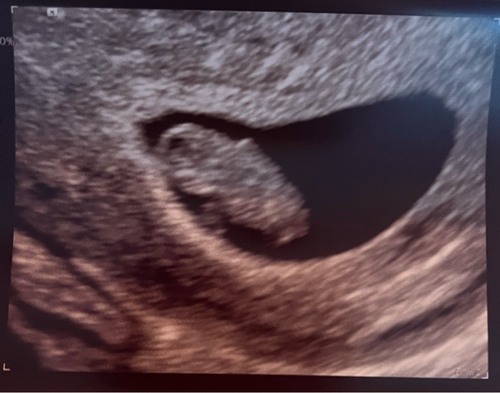

Hier de echo van 7+5 van het zijaanzicht via inwendige echo. Ik kan er niet veel van maken nog 😂😂